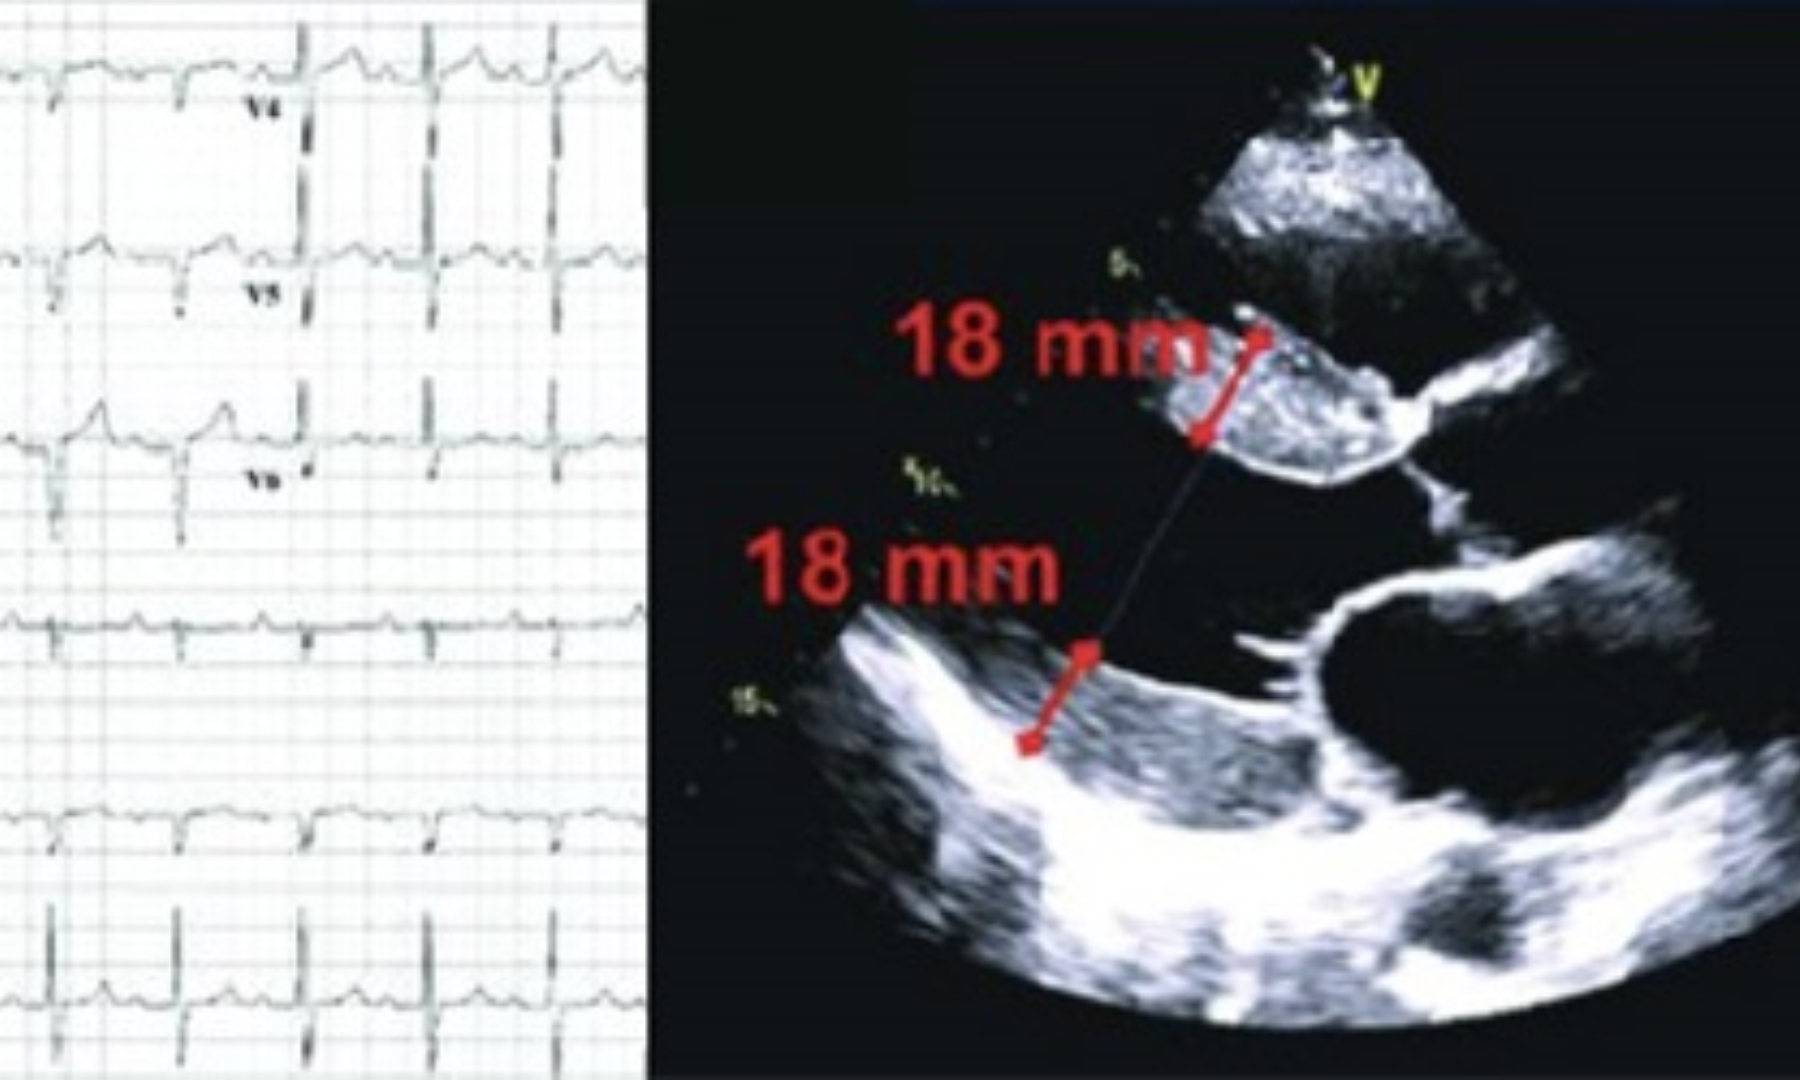

Obiettivo principale dei test genetici è prevenire il rischio di morte improvvisa. Il loro focus, il nucleo familiare e le eventuali mutazioni genetiche responsabili delle cardiomiopatie.